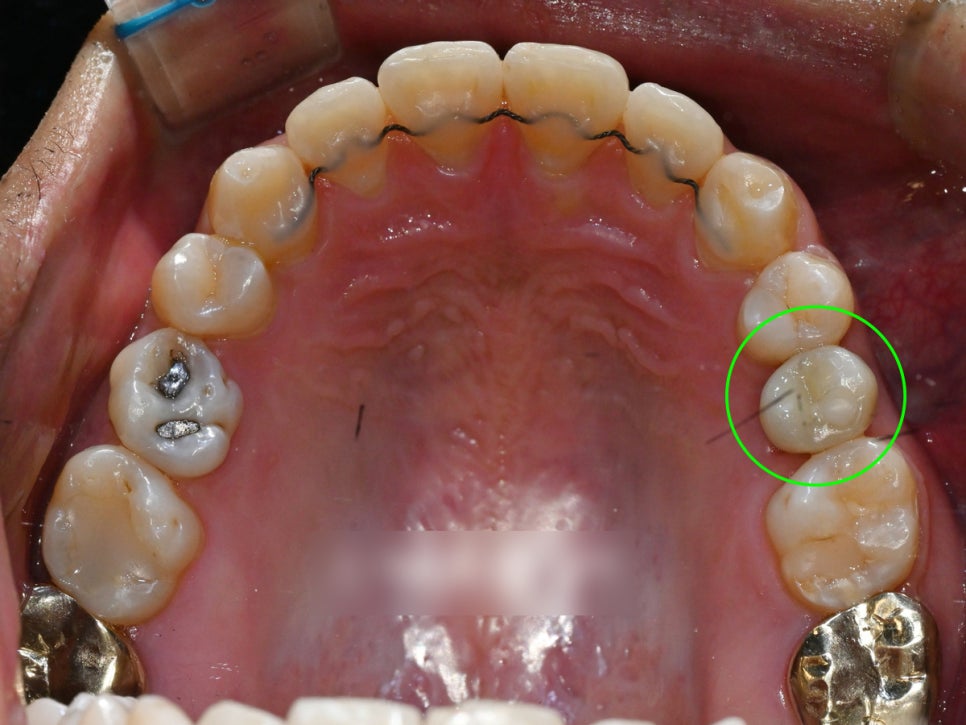

내원 당시 사진

언뜻 봤을 땐 치열이 고른편이라

‘교정이 꼭 필요한가?’ 싶을 수 있지만,

이 환자는 다른 부분이 있습니다.

당시, 위쪽 어금니 하나를

일찍 상실하여 임플란트 식립 예정인

상황이라는 점입니다.

그러나 이 상태가 꽤 오랜기간

방치가 되었는지 앞 어금니가 이동되면서

발치 공간이 줄어든 상태였습니다.